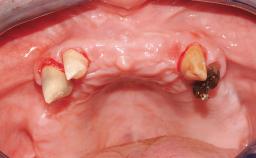

Immediate Loading of Eight Implants in the Maxilla and Six Implants in the Mandible and Final Restoration with Three-Unit and Four-Unit FDPs

Extensive scientific evidence has confirmed that immediately loaded implants with fixed full-arch provisional restorations can osseointegrate with success rates similar to conventionally or delayed loaded implants. A number of immediate-provisionalization techniques for edentulous jaws have been described. Some protocols differ when it comes to prefabricated provisional templates versus complete denture conversion; intrasurgical impressions versus direct relining; and cemented versus screw-retained provisional restorations. In this context, complete-denture conversion has been proposed for either intrasurgical impressions or direct relining. Another possibility is the utilization of a prefabricated provisional to be adapted either in the mouth (by direct relining) or in the laboratory (on a working model obtained from an intrasurgical impression).

Defining Characteristics Fully edentulous upper jaw to be rehabilitated with four or more implants

Modality 6+ implants with immediate loading